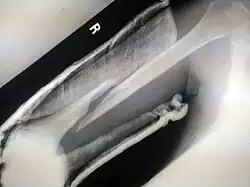

![]() | |

| Internal and external views of an arm with a compound fracture, both before and after surgery | |